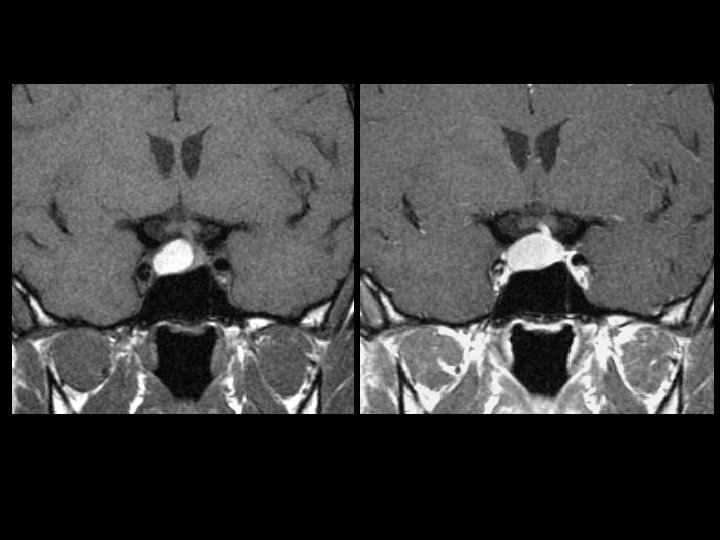

Cavernoma of the Spine • • • Findings: – “popcorn-like” intramedullary lesion in the conus – T 2: faint high signal – T 2: high signal centrally, dark rim, and high signal peripherally a. k. a. Cavernoma, cavernous hemangioma, and capillary hemangioma Congenital abnormal cluster of capillaries and venules that periodically bleed Signal characteristics are that of blood in different stages Angiographically occult Look for multiple lesions on GRE